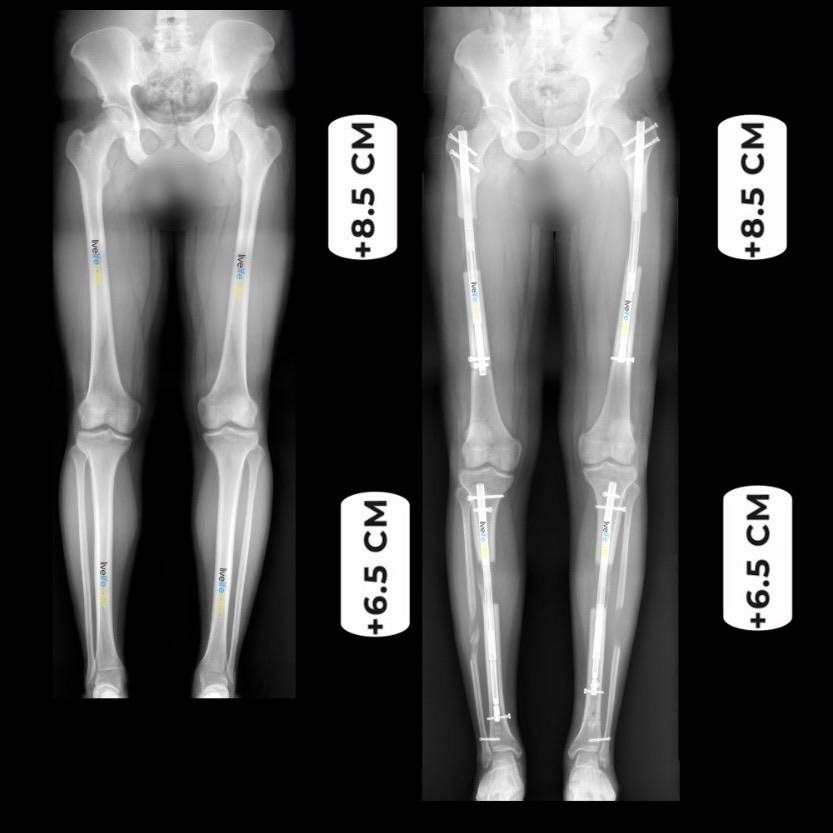

Quadrilateral Lengthening Before and After

It’s worth noting that the maximum achievable lengthening is still considered to be up to 16cm. However, the specific lengthening amounts may vary from person to person based on individual factors such as bone quality, soft tissue condition, and patient goals. As a general guideline, femur lengthening can be around 8cm, while tibia lengthening can range from approximately 6-7cm. These recommendations can be further customized and tailored to the unique needs and circumstances of each patient, with close consideration given to their overall health, functional requirements, and desired outcomes.